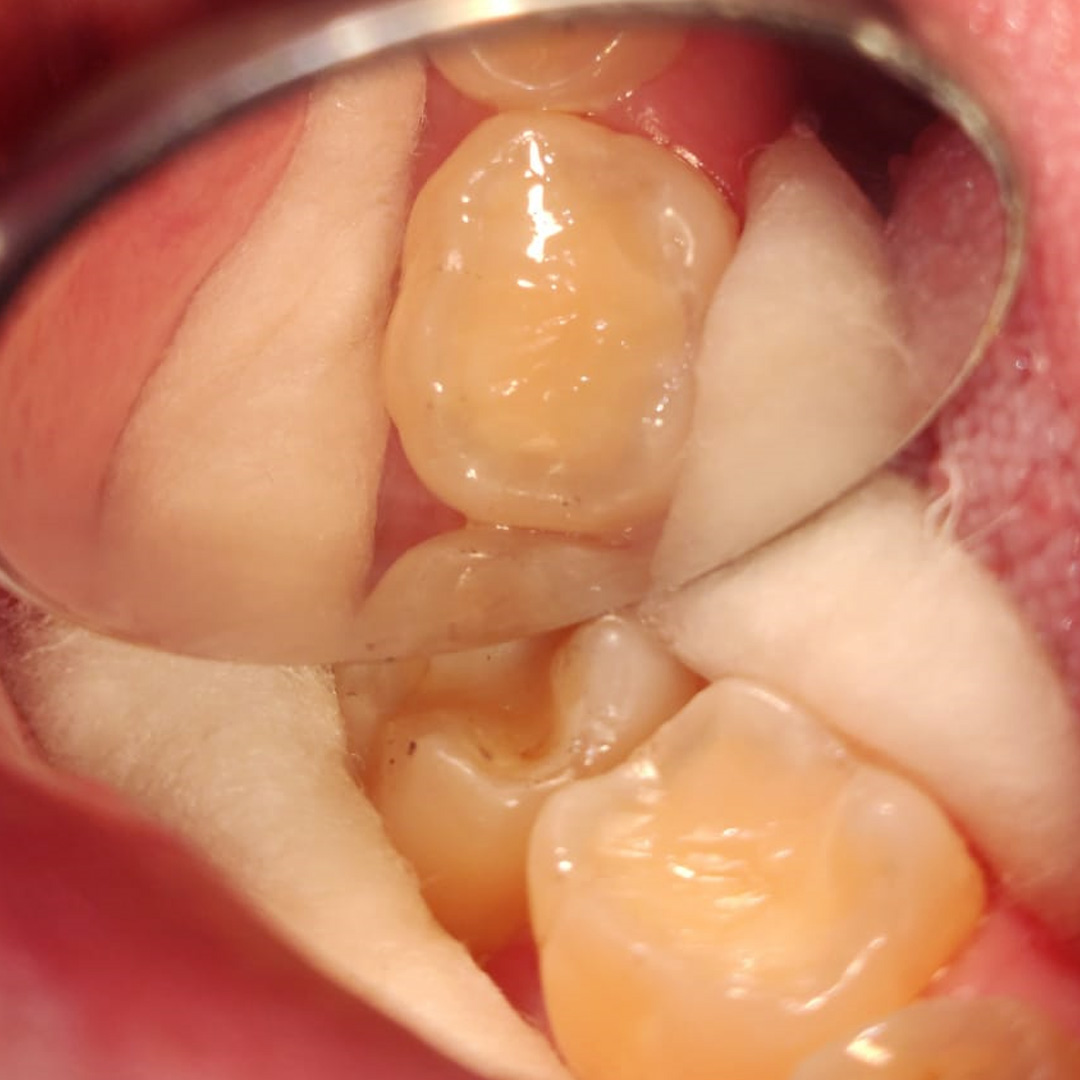

До и после лечения

Пациент обратился в клинику с жалобами на эстетику в области нижнего жевательного зуба справа. Отмечена небольшая чувствительность при приёме холодной пищи. После обработки полости под контролем кариес маркера, был выявлен глубокий кариес, дно и стенки полости плотные, пульпа не затронута. Наш специалист Григорьев Пётр Игоревич поставил диагноз: хронический глубокий кариес 3.6 зуба. После этого был составлен и утверждён план лечения.

В ходе лечения были проведены следующие работы:

- с использование системы коффердам проведена механическая обработка полости

- медикаментозная обработка с использованием хлоргексидина 2%

- поставлена пломба Fuji II A3

- проведена проверка окклюзионных контактов, шлифовка и полировка